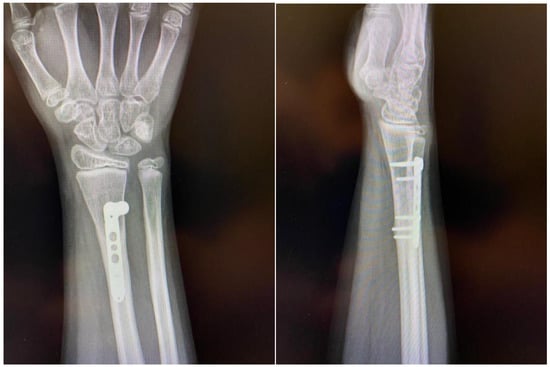

Due to the fact that orthopedic maneuvers were not efficient, the patient was taken to the operating room and the maneuvers repeated under general anesthesia, but this was also inefficient. A mini open reduction technique was applied, in which a K-wire was introduced into the fracture site through a <1 cm skin incision and used as a lever to facilitate reduction. Once reduction was obtained under fluoroscopy, the fracture was fixed percutaneously using two crossed K-wires, obtaining satisfactory stability and the final result (Figure 2).

Figure 2. Radiological images obtained post-operatively. (A): AP view of the distal forearm, demonstrating good reduction of the fractures and fixation of the radius with two crossing K-wires according to AO pediatric technique. (B): Lateral view with very good reduction of the volar angulation of the radius, with slight but acceptable displacement of the ulna.